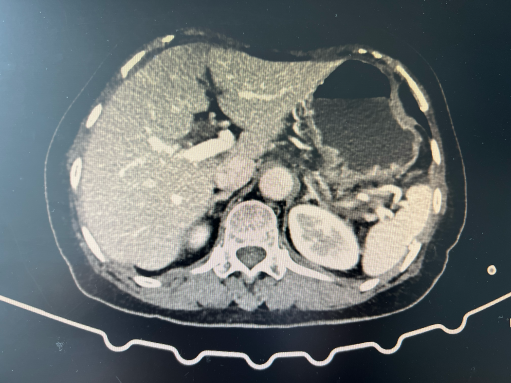

术前影像